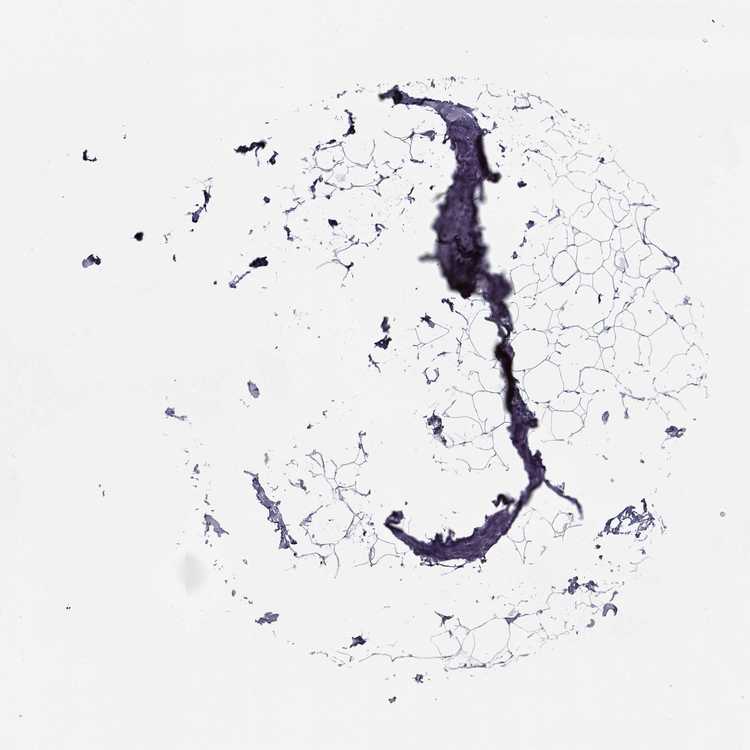

BREAST - Antibody stainingi

Antibody staining in the annotated cell types in the current human tissue is reported as not detected, low, medium, or high, based on conventional immunohistochemistry profiling in selected tissues. This score is based on the combination of the staining intensity and fraction of stained cells.

Each image is clickable and will lead to virtual microscopy that enables deeper exploration of all samples and also displays staining intensity scores, fraction scores and subcellular localization as well as patient and tissue information for each sample.

Antibody HPA073560

Adipocytes Not detected

Glandular cells Not detected

Myoepithelial cells Not detected